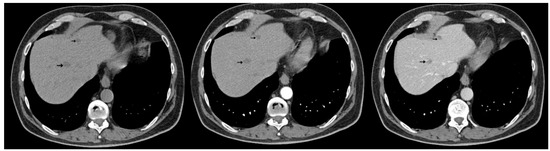

Synchronous Pulmonary and Cecal High-Grade Neuroendocrine Carcinomas Presenting as Hepatic Metastases: A Diagnostic Challenges and Literature Review

Background and Clinical Significance: Neuroendocrine neoplasms (NENs) are a group of malignancies that may remain clinically silent for many years. The presence of hepatic metastases can be the first clue leading to diagnosis. Case Presentation: We report the case of a 67-year-old man [...] Read more.

Background and Clinical Significance: Neuroendocrine neoplasms (NENs) are a group of malignancies that may remain clinically silent for many years. The presence of hepatic metastases can be the first clue leading to diagnosis. Case Presentation: We report the case of a 67-year-old man with intermittent tiredness and suspicious hepatic nodules detected on routine abdominal ultrasound. Contrast-enhanced ultrasonography showed arterial hyperenhancement with early washout, suggestive of metastases. Synchronous high-grade neuroendocrine carcinomas (NECs) of the lung and cecum were identified. Although the liver lesions were initially presumed to arise from the cecal tumor, liver biopsy immunohistochemistry was TTF-1 positive/CDX2 negative, whereas the cecal lesion was TTF-1 negative/CDX2 positive. This mutually exclusive immunophenotype confirmed two separate primary carcinomas. Given the high-grade histology, the patient received platinum-based chemotherapy and achieved a partial response. Conclusions: This case illustrates the diagnostic complexity of synchronous lesions and highlights the “mirage of the first lesion” phenomenon, in which the initially detected tumor may not represent the true primary site. A comprehensive, multidisciplinary strategy is crucial for establishing the correct diagnosis and guiding optimal management. Full article

(This article belongs to the Special Issue Diagnosis and Management of Neuroendocrine Tumors)